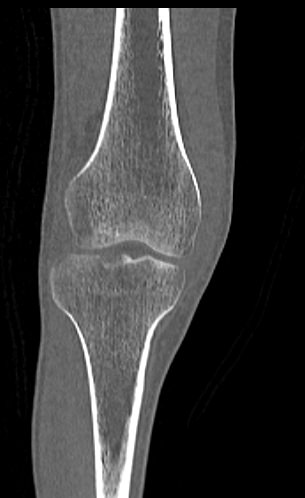

Одним из наиболее информативных методов исследования коленных суставов является мультиспиральная компьютерная томография. КТ относится к лучевым методам исследования и основана на применении ионизирующего излучения с последующей цифровой обработкой данных, полученных при КТ-сканировании.

В наших медицинских центрах обследование коленного сустава проводится на современных мультиспиральных компьютерных томографах последнего поколения TOSHIBA AQUILION. При помощи рентгеновских лучей аппараты послойно сканируют в разных плоскостях исследуемую область с толщиной среза от 0,5 мм. В результате получаются детальные снимки и цифровые трехмерные изображения коленного сустава в мельчайших подробностях. Помимо точности и достоверности диагностики современные компьютерные томографы обеспечивают для пациента минимальную дозу рентгеновского облучения.

Мультиспиральная компьютерная томография дает возможность оценить структуру костной ткани, выявить переломы, воспалительные изменения, участки деструкции костей и диагностировать опухолевые образования. Мультиспиральная КТ часто применяется в ортопедии и травматологии. За счет быстроты, доступности и неинвазивности (то есть обследование выполняется без вмешательства в организм) метод незаменим при травмах сустава, а также при планировании оперативных вмешательств, например, в случае эндопротезирования сустава. В послеоперационном периоде КТ помогает оценить эффективность проведенной операции, вовремя выявить осложнения и отследить процесс восстановления.

Что показывает КТ коленного сустава

- переломы костей;

- артроз;

- артрит;

- скопление жидкости в суставе;

- кисту Бейкера;

- костные наросты на поверхности сустава;

- новообразования

- полные или неполные вывихи — по смещению образующих сустав элементов относительно друг друга;

- деформирующий остеоартроз, ревматический полиартрит

- злокачественную или доброкачественную опухоль

- гемартроз

- абсцесс.